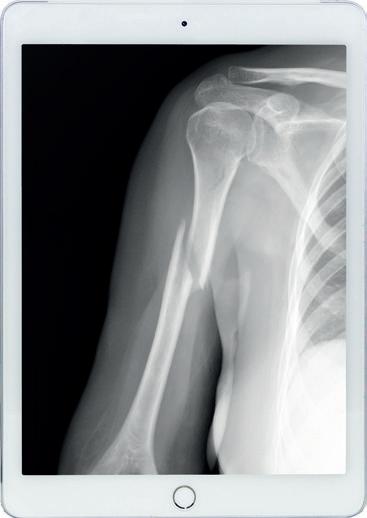

It’s not funny to break your Humerus!

There is nothing funny about living with a broken arm, but lots of us have to while we wait for the bone to heal. A common fracture is to the top of the Humerus bone just below the shoulder joint.

In fact, about 5% of all fractures are proximal humeral fractures in the upper arm. A classic way to break this bone is to fall on an outstretched arm and this injury will happen to twice as many women as men.

The good news is that these fractures heal well if they are not displaced so treatment is with rest in a sling with a phased exercise programme to regain function. More complex fractures where the bone ends are out of

alignment may need surgery to pin them together. Pain control is important in the first few weeks so do use medication, if necessary, as advised by your doctor.

It is vitally important to continue to exercise as pain allows. There is the potential to develop problems at other joints in the upper limb due to the swelling and bruising in the arm affecting function. There is also the potential to develop a frozen shoulder and this will take up to 2 years to heal – a case where prevention is definitely better than cure! A rehab programme may look something like this, but do take advice from your own Physio or Consultant.

For an un-displaced proximal humeral fracture rest out of the sling as much as possible. Do let your arm hang down so that gravity can help keep the bone in good alignment. Exercise “little and often” through the day so you do not get too tired or too painful. Exercises for the first 3 weeks will include moving your fingers, wrist and elbow to keep these joints mobile, keep the muscles moving and help get rid of swelling. You will also be shown how to do pendular exercises – gently swinging your arm forwards and backwards, side to side and in circles - all to help keep the shoulder from becoming stiff. Always remember to never push into pain.

From 3 – 6 weeks the exercises are progressed to include active assisted exercises where you try to move your arm more with the help of your other arm, a stick, or sliding your hand on a table to help your shoulder move more. You should avoid lifting anything heavy, such as a full kettle, for the first 4 – 6 weeks after fracture. After 6 weeks the bone is healed and so exercises against resistance can be introduced to build up muscle strength. It is normal at this stage to still have some discomfort and some difficulty moving your arm. The big question is always “when can I drive again?” Most people manage this about 6 – 8 weeks after the injury when they no longer need to use the sling at all and they feel they can control the car. A fractured humerus is no laughing matter but they heal well given the right encouragement.